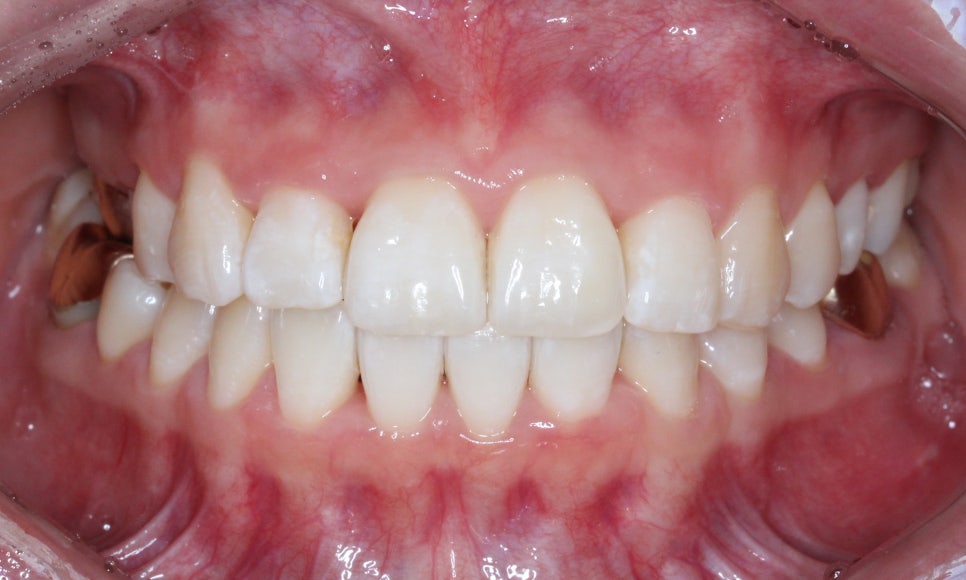

첫 방문

처음 방문 하셨을 때 모습입니다.

오른쪽 두번째 앞니가 거꾸로 물리는 상태이고

(사진상 왼쪽)

윗니가 전체적으로 삐뚤빼뚤한 것이 보입니다.

잘 보이실진 모르겠지만,

우측 구치부는 전반적으로

거꾸로 물리는 양상이 보입니다.